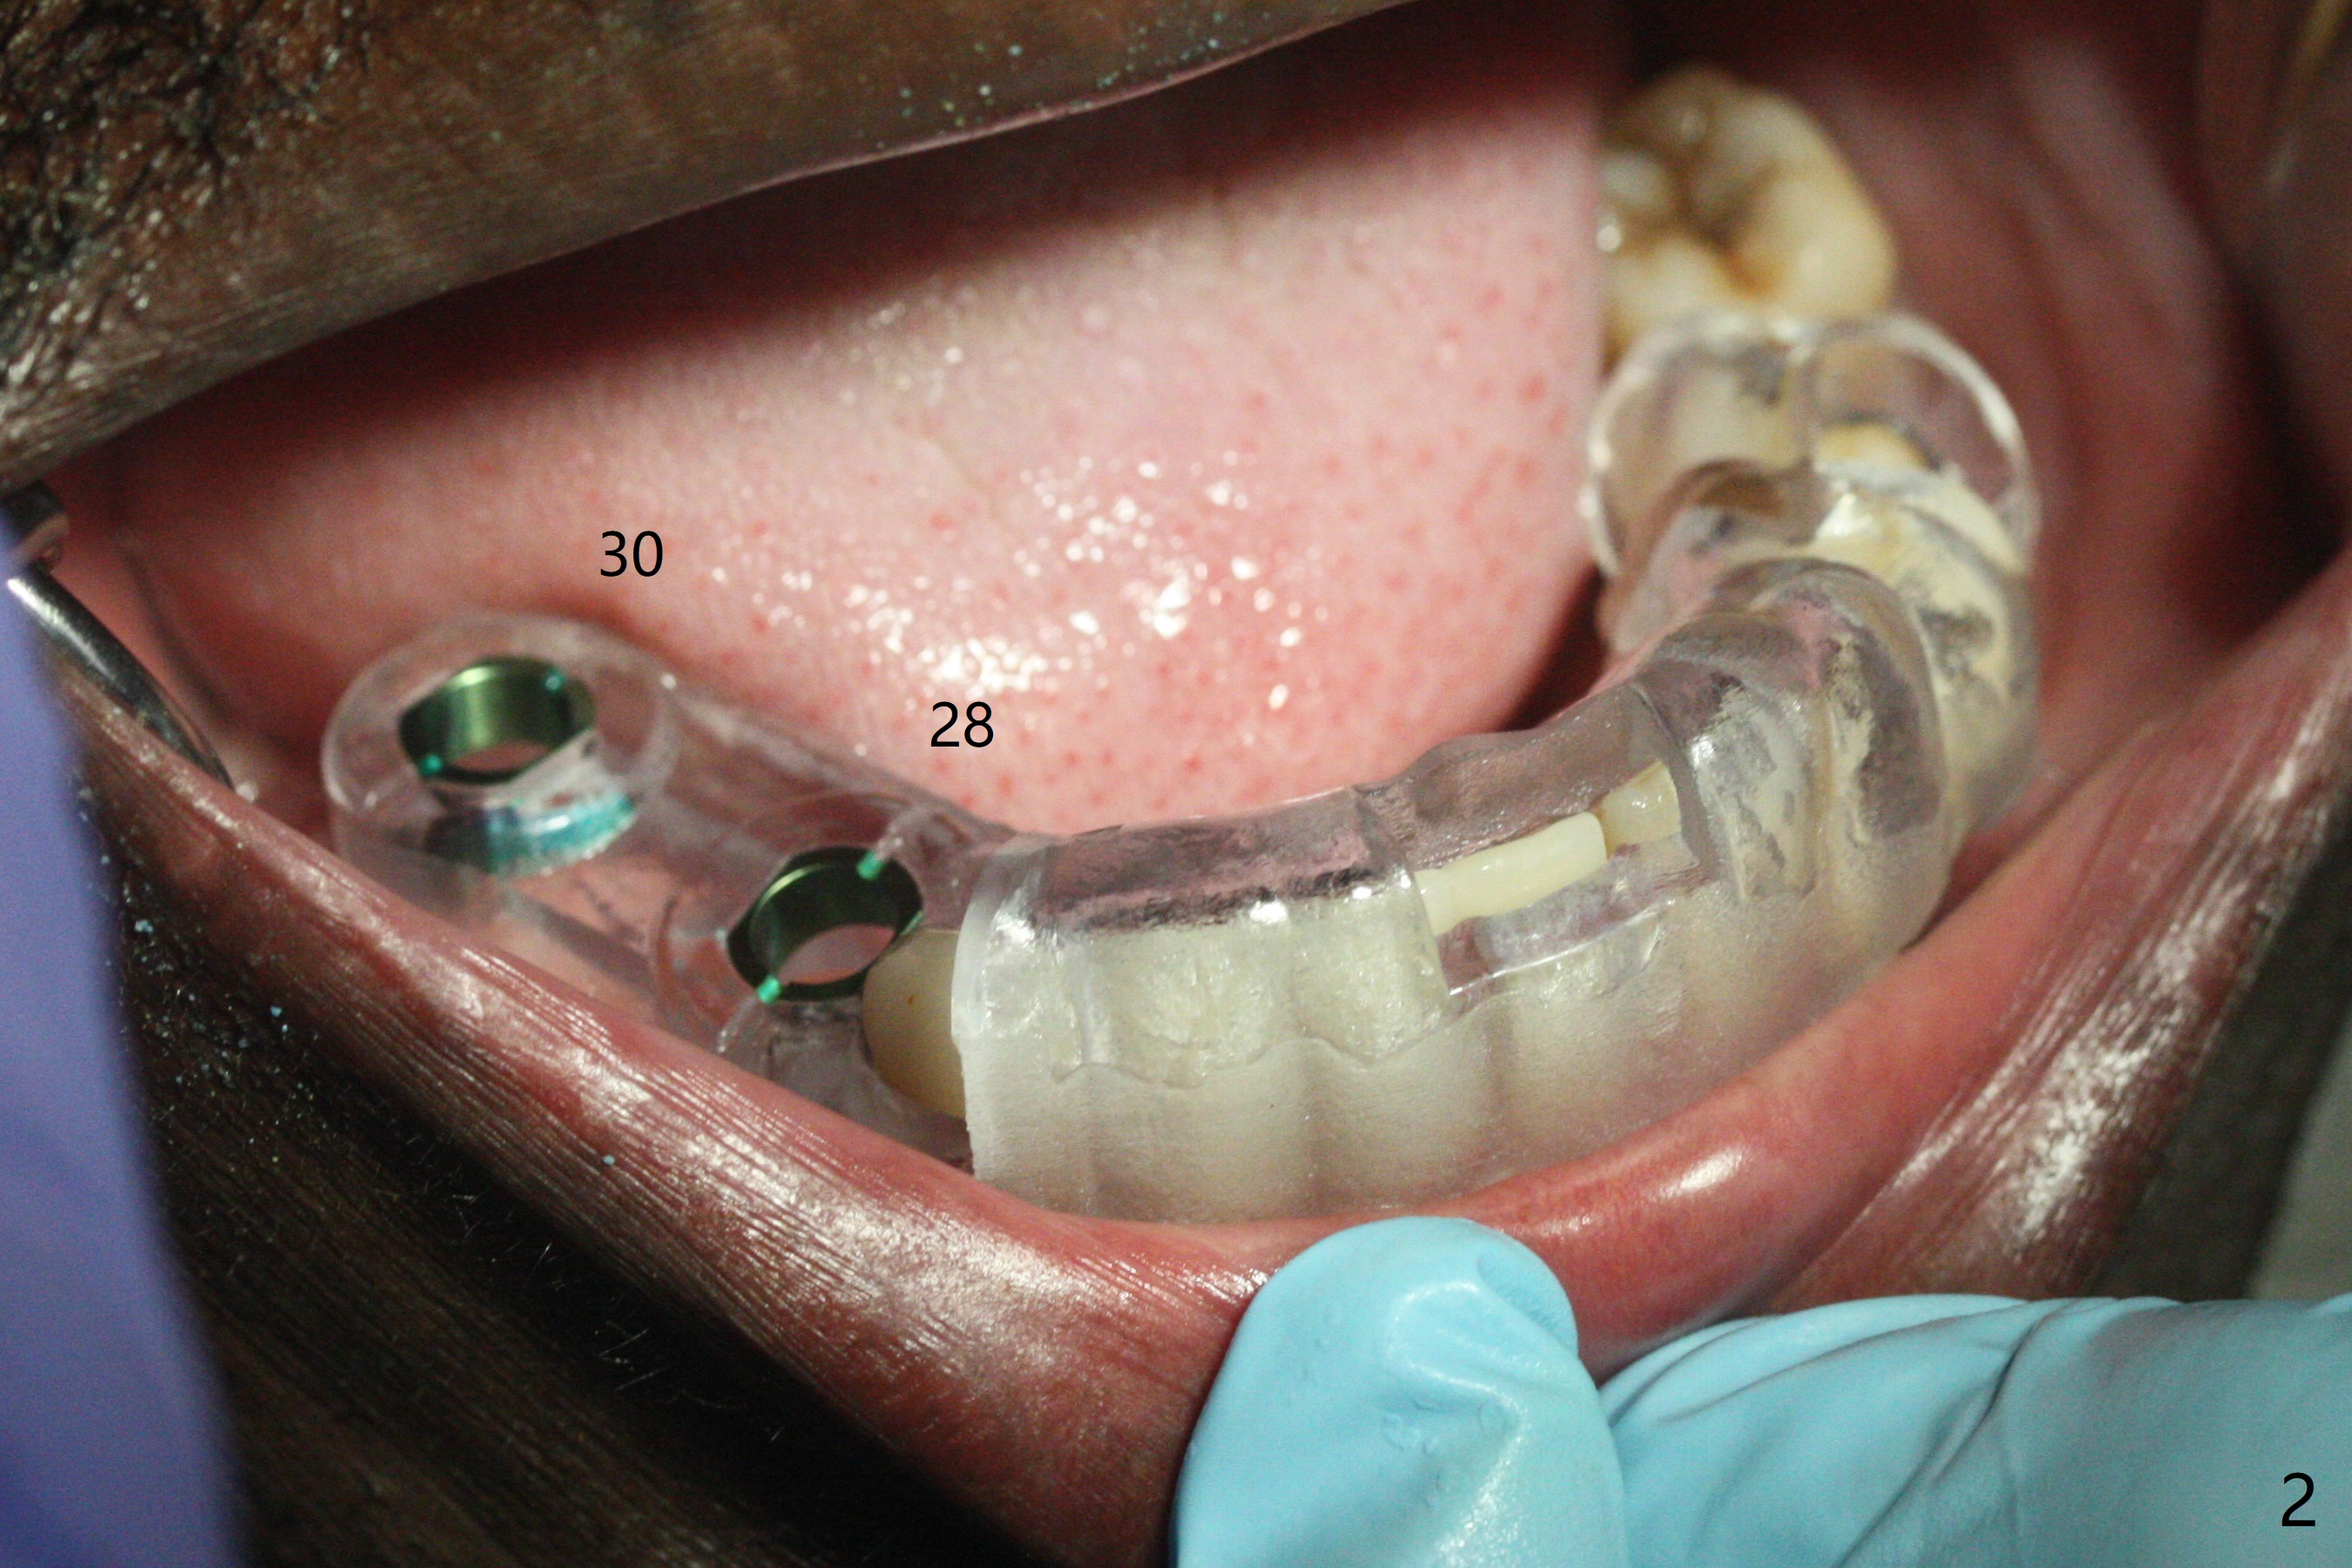

The ridge post bone graft (#28) and socket preservation (#30) is wide. Using a surgical guide (Fig.2), tissue punch is used to initiate osteotomy without compromising the keratinized gingiva (Fig.3). With no stop fixture mount for a 4.5x11.5 mm implant being placed at #28, the osteotomy at #30 is much easier. A 5x17 mm Tatum tapered tap is inserted with the guide and then without the guide. Finally the 5x14 mm tissue level implant is placed free hand (Fig.4). With underdrilling at #30 (4x10 and 4x11.5 instead of 4.5x10 and 4.5x11.5), primary stability is high. So is #28. Abutments are placed for periodontal dressing (Fig.5).